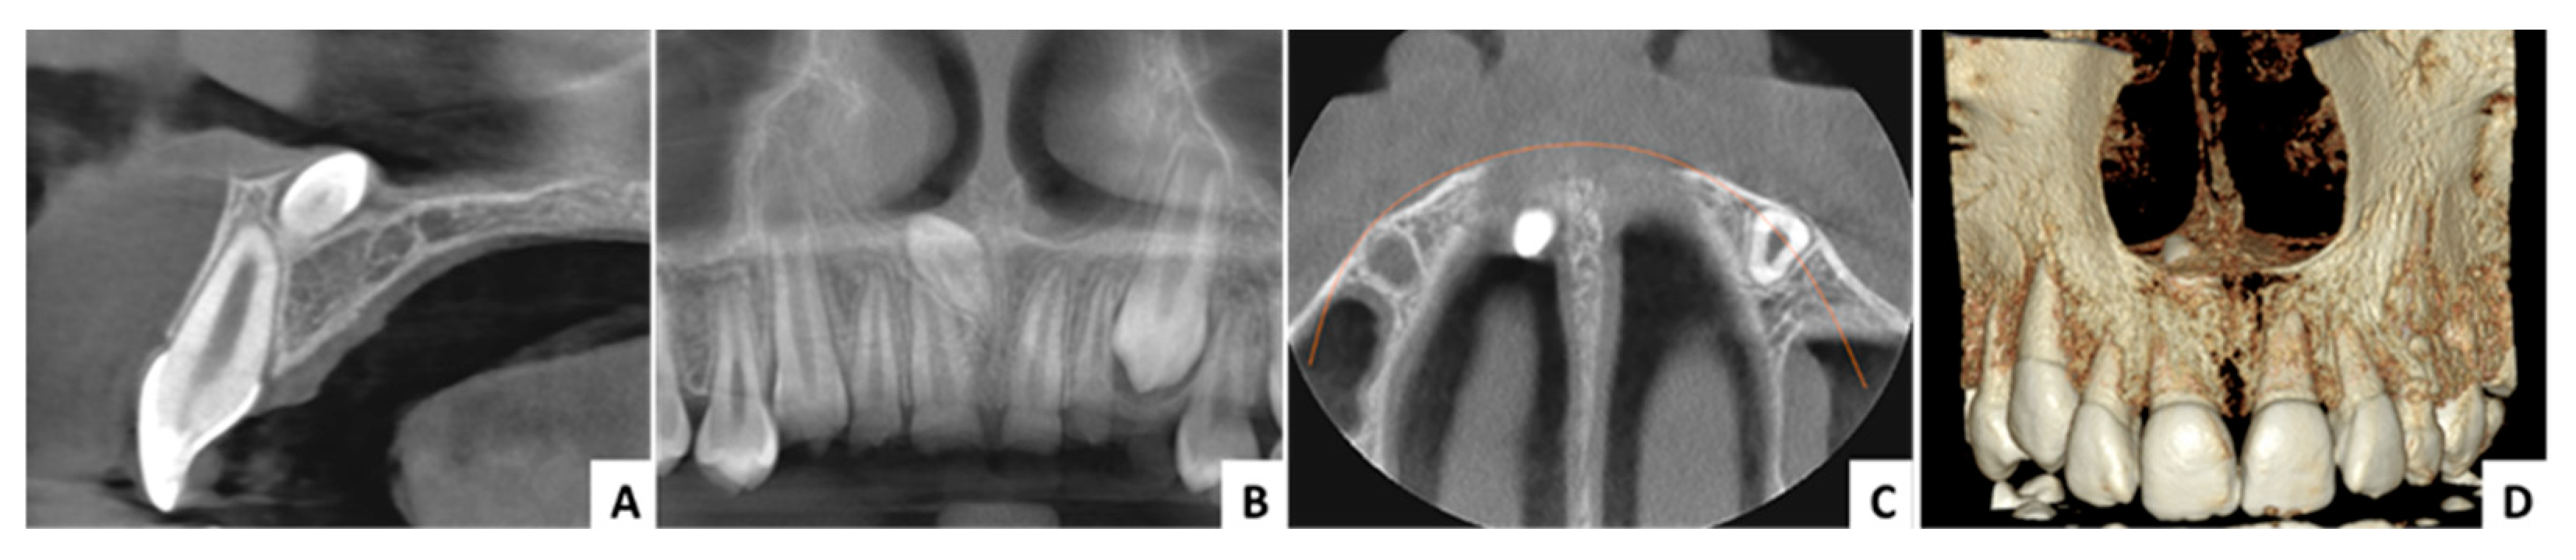

3.1. Case 1 (Figure 3, Figure 4 and Figure 5)

| Case No. | 1 | 2 | 3 |

|---|---|---|---|

| Age (years)/sex | 29/F | 11/M | 16/M |

| Angle formed by the mesiodens axis with the nasal floor | 85.93° | 143.5° | 144.4° |

| Distance from the ANS (mm) | 8.98 | 8.11 | 13.22 |

| Distance to mesiodens from buccal aspect (mm) | 4.71 | 3.70 | 3.84 |

| Distance to mesiodens from palatal aspect (mm) | 6.43 | 5.47 | 6.82 |

| Relation with nasal cavity | Covered with bone | Submucosally | Covered with bone |

| Position regarding nasopalatine canal | In front | In front | In front |

| Operation time (minutes) | 30 | 28 | 31 |

| Complications | No | No | No |